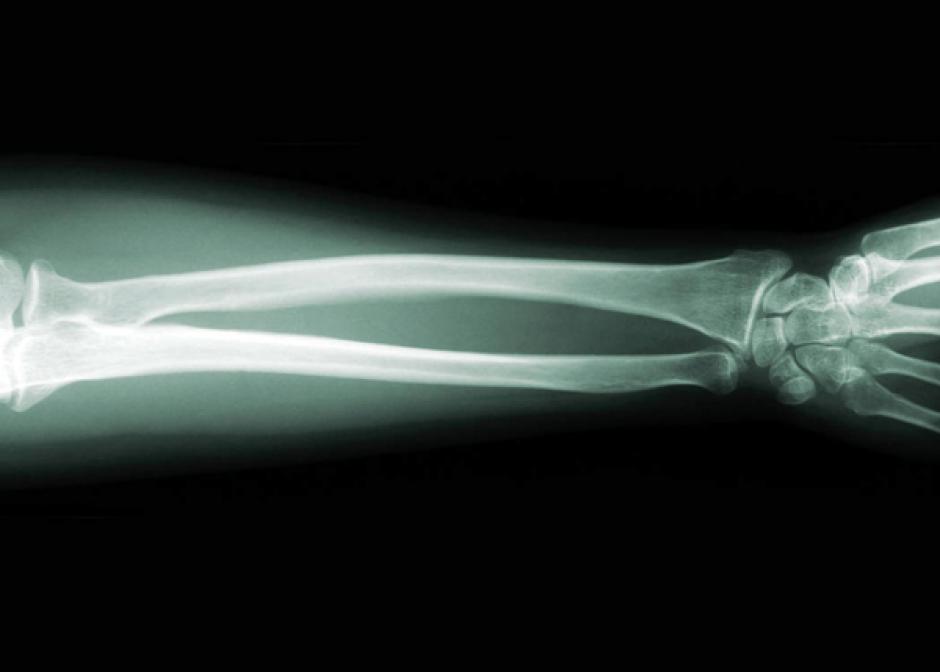

Un grupo de científicos belgas ha desarrollado una innovadora técnica para reconstruir partes de hueso humano dañado a partir de células madre extraídas de la grasa corporal del paciente, según dan a conocer hoy los medios del país.

Este método, hasta ahora nunca utilizado, podría revolucionar el tratamiento de las fracturas óseas y de enfermedades como el cáncer óseo, según afirmaron los artífices de este proyecto científico de la Universidad Católica de Lovaina (norte de Bélgica).

La técnica se basa en el cultivo de células madre extraídas de la grasa corporal del paciente, con las que se crea una especie de pasta moldeable y válida para ser reimplantada en las partes de hueso dañadas.